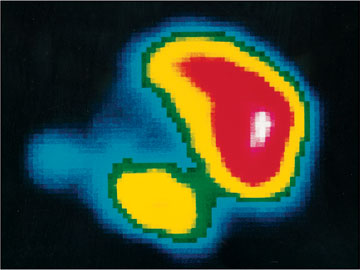

Rheumapatienten, bei denen einzelne Gelenke besonders schwer betroffen sind, können vom Verfahren der Radiosynoviorthese profitieren. Bei dieser nuklearmedizinischen Therapie wird ein Radiopharmakon direkt in das schmerzende, ruhiggestellte Gelenk gespritzt. Dort zerstört es die Zellen der wuchernden, entzündeten Gelenkinnenhaut (Synovia), die die Schmerzen verursacht. Zum Einsatz kommen dabei radioaktive Substanzen (Beta-Strahler), deren Strahlung im Gewebe nur eine Reichweite von wenigen Millimetern hat. Dadurch bleibt die Wirkung auf die entarteten Zellen der Gelenkinnenhaut beschränkt. Das umliegende Gewebe wird nicht geschädigt. Die Radiosynoviorthese kann, sollte die Gelenkinnenhaut erneut wuchern, problemlos wiederholt werden. |